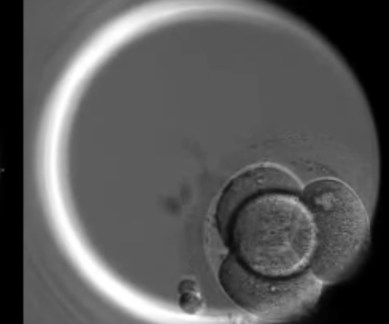

They used genome editing technique called CRISPR/Cas9 to stop a key gene from producing a protein called OCT4, which normally becomes active in the first few days of human embryo development. After the egg is fertilised, it divides until at about seven days it forms a ball of around 200 cells called the ‘blastocyst’.

To inactivate OCT4, they used CRISPR/Cas9 to change the DNA of 41 human embryos. After seven days, embryo development was stopped and the embryos were analysed. The embryos used in the study were donated by couples who had undergone in vitro fertilisation (IVF) treatment, with frozen embryos remaining in storage.